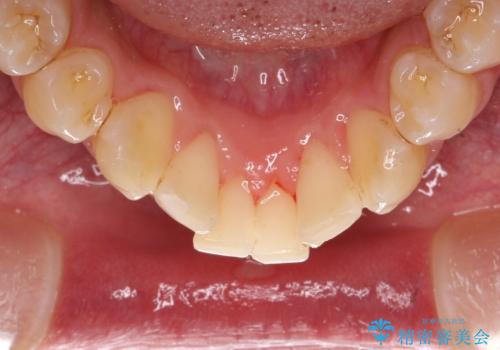

茶渋による着色と下の前歯の裏側のべったり歯石

コーヒーやお茶をよく飲む患者様で、その影響か全体的に茶渋が見られました。

下の前歯は少しがたつきがあるため、歯石がたまりやすいように見られます。

着色落としをメインに歯石も落とすためPMTC(エアフロー)にて施術いたしました。

水と風と細かいパウダーを使用して歯の表面の汚れを落とすクリーニングです。

着色だけではなく、プラーク(歯垢)除去も可能になります。

細かいパウダーが歯面全体にいきわたりやすく素早くお掃除が可能なので30分コースで行いました。